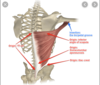

latissimus dorsi location

attachments of latissimus dorsi

functions of latissimus dorsi

innervation of latissimus dorsi

blood supply of latissimus dorsi

anatomical relationships of latissimus dorsi

clinical considerations of latissimus dorsi